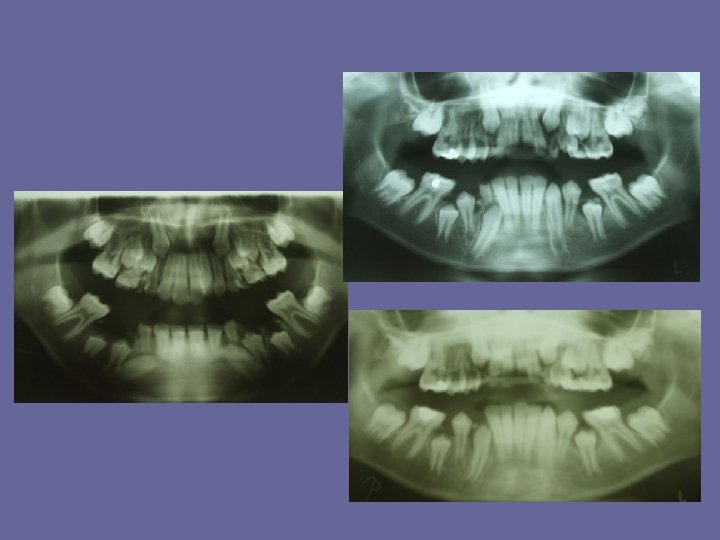

THE MIXED DENTITION • At the age of 6 years permanent teeth, usually the first molars or lower central incisors start to erupt. • As in the case of the deciduous teeth, eruption times are very variable and a range of 18 months on either side is not unusual. • There also some sex differences in the age of eruption. Girls are 1/2 year ahead of boys. • During this century there has been a tendency towards earlier eruption of permanent teeth in the developed countries ( "secular trend" ). It has mainly been due to the earlier onset of puberty, and indirectly to better child health and nutrition

THE MIXED DENTITION Typical ages of eruption: • first molar. . . 6 -7 years • central incisor. . . 6 -7 years • lateral incisor. . . 7 -8 years • canine. . . 9 -13 years • premolars. . . 9 -13 years • second molar. . . 11 -14 years • third molar. . . 17 -30 years The permanent teeth erupt first in mandible and then in maxilla except the premolars which erupt first in maxilla.

THE MIXED DENTITION

THE MIXED DENTITION • At the time of eruption 2/3 of the root is generally formed. Thereafter, 1, 5 -3 years are needed to complete root length and even longer to close the root apices to the mature size.